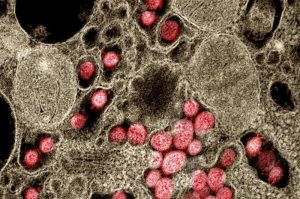

SARS-CoV-2: rivelato il meccanismo molecolare delle tempeste di citochine

SARS-CoV-2-Immagine Credit Public Domain- Di Zhang Nannan, Accademia cinese delle scienze- SARS-CoV-2 stabilizza gli mRNA dell’ospite per indurre una tempesta…